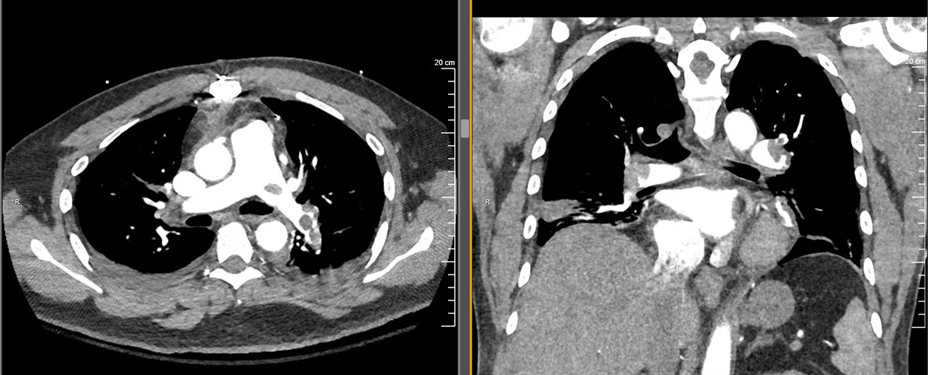

The ultrasound demonstrated a dilated RV with decreased function and septal bowing on the PSAX view. This combined with his vital signs, history and exam was most concerning for a high-risk PE. Prior to the ultrasound the differential would be quite broad, with the other most concerning life-threatening diagnoses being cardiac tamponade, pneumonia, ACS, and new-onset heart failure. The ultrasound was key in narrowing the differential diagnosis in this case. The patient was moved immediately to the CT scanner once the ultrasound was performed. Images are shown below.

This patient had bilateral main pulmonary artery emboli with areas of the main pulmonary artery that were essentially completely occluded. He also had CT evidence of R heart strain and evidence of developing pulmonary infarctions. The ED team interpreted the CT while in the scanner with the patient and made a treatment decision shortly after.